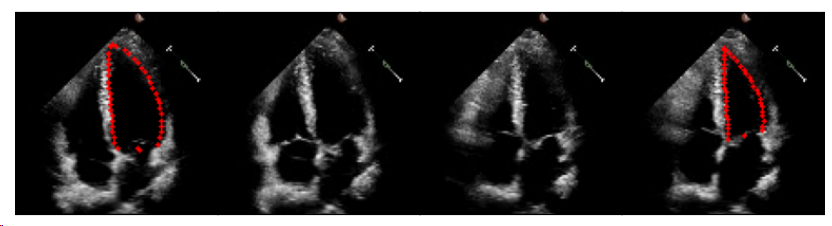

EchoNet-Dynamics是最大的公开2D+Time心脏超声心动图,其显示了人体心脏的顶部四腔视图。提供了约10,030个心脏超声心动图视频,固定帧大小为112 x 112。

视频长度从28帧到1002帧不等,涵盖多个心跳周期,但只有两个被注释(ED和ES帧)。图1中给出了示例超声心动图序列